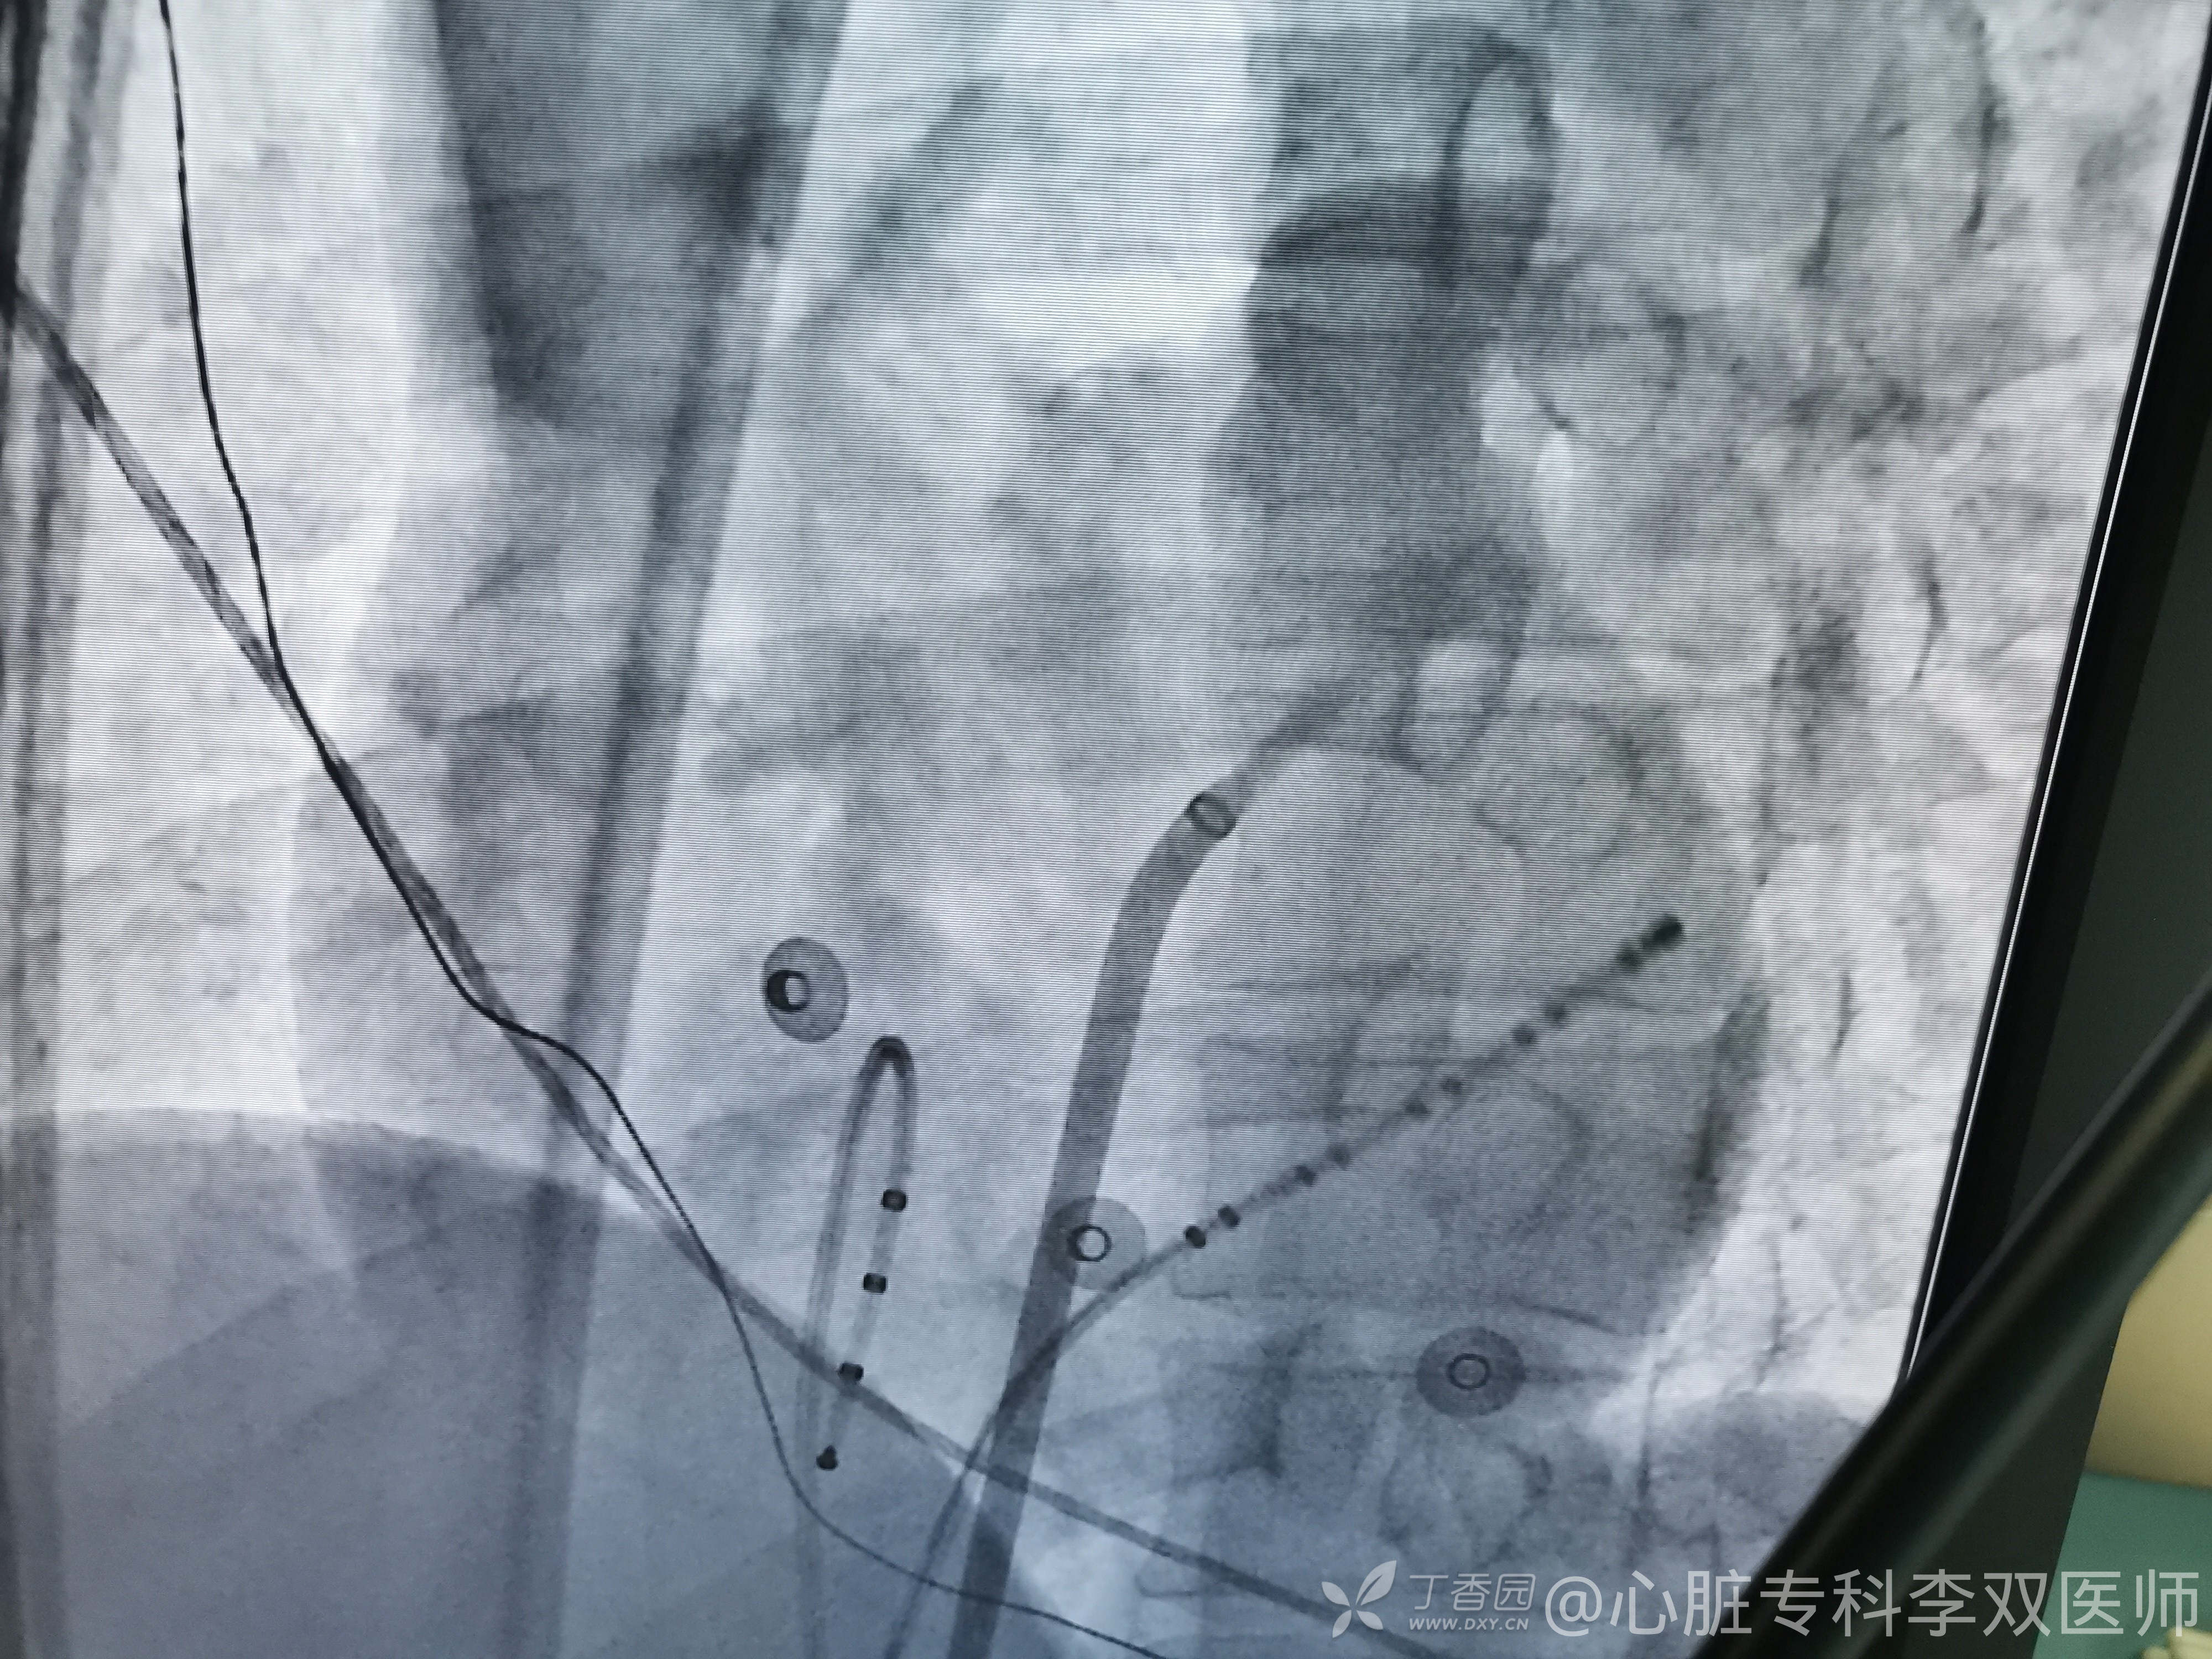

今天准备电生理检查和冠脉造影一起做,看看诱发出什么。准备尽可能省点钱,希氏束四级电极不准备用。

置管过程就见到室早逆传,比较轻松就确诊了,左侧旁道(高位游离壁)

用的穿间隔打(不想去惹股动脉),用的ST导管,带压力指示,打的放心。

穿房间隔专门靠上,比较nice,到位和帖靠都比较方便,两枪就打停旁道(第一枪放电20秒没反应,应该是帖靠的问题,我们再次校正压力后第二枪在差不多同样位置直接打掉,一直保持7-15g压力)。

消融后房侧室侧都巩固一下,有ST导管就是放心。然后观察。